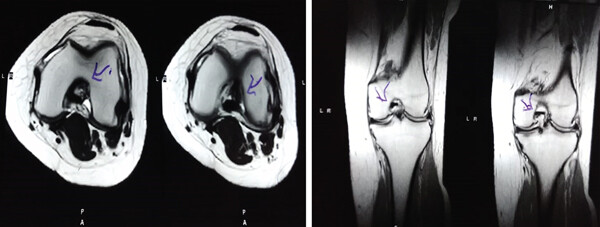

MRI檢查發(fā)現(xiàn)半月板損傷處修復(fù):3D MRI 顯示 2 年時(shí)半月板撕裂難以辨別。

結(jié)論:滑膜間充質(zhì)干細(xì)胞移植后,2年的隨訪中,患者的關(guān)節(jié)功能改善,MRI檢查發(fā)現(xiàn)半月板損傷處恢復(fù),沒(méi)有發(fā)生導(dǎo)致研究終止的重大不良事件。可以達(dá)到干細(xì)胞治療半月板損傷長(zhǎng)期療效的目標(biāo)。

影像學(xué)檢查:4例MM皮瓣撕裂患者在治療前后交界區(qū)中央?yún)^(qū)域出現(xiàn)缺損,但其中2例患者該區(qū)域完全恢復(fù)穩(wěn)定光滑狀態(tài),另2例患者該區(qū)域部分恢復(fù)。治療前后交界區(qū)中央?yún)^(qū)域皮瓣撕裂的關(guān)節(jié)鏡評(píng)分為0.3±0.5,治療后為4.3±2.1,治療后評(píng)分顯著升高。2例患者原有放射狀MM撕裂在治療一年后愈合。

關(guān)節(jié)功能:治療后4周和52周的Lysholm評(píng)分顯著高于治療前。

結(jié)論:間充質(zhì)干細(xì)胞移植后,隨訪24個(gè)月內(nèi),患者影像學(xué)和關(guān)節(jié)功能顯著改善,未發(fā)生嚴(yán)重不良事件。可以達(dá)到干細(xì)胞治療半月板損傷長(zhǎng)期療效的目標(biāo)。